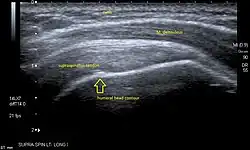

Ultrasound

There are several advantages of ultrasound. It is relatively cheap, does not emit any radiation, is accessible, is capable of visualizing tissue function in real time, and allows the performance of provocative maneuvers in order to replicate the patient’s pain.[28] Those benefits have helped ultrasound become a common initial choice for assessing tendons and soft tissues. Limitations include, for example, the high degree of operator dependence and the inability to define pathologies in bones. One also has to have an extensive anatomical knowledge of the examined region and keep an open mind to normal variations and artifacts created during the scan.[29]

After the introduction of high-frequency transducers in the mid-1980s, ultrasound has become a conventional tool for taking accurate and precise images of the shoulder to support diagnosis.[31][32][33][34][35]

Adequate for the examination are high-resolution, high-frequency transducers with a transmission frequency of 5, 7.5, and 10 MHz. To improve the focus on structures close to the skin an additional "water start-up length" is advisable. During the examination the patient is asked to be seated, the affected arm is then adducted and the elbow is bent to 90 degrees. Slow and cautious passive lateral and/or medial rotations have the effect of being able to visualize different sections of the shoulder. In order to also demonstrate those parts which are hidden under the acromion in the neutral position, a maximum medial rotation with hyperextension behind the back is required.[36]

To avoid the different tendon echogenicities caused by different instrument settings, Middleton compared the tendon’s echogenicity with that of the deltoid muscle, which is still lege artis.[37][38]

Usually the echogenicity compared to the deltoid muscle is homogeneous intensified without dorsal echo extinction. Variability with reduced or intensified[39] echo has also been found in healthy tendons. Bilateral comparison is very helpful when distinguishing and setting boundaries between physiological variants and a possible pathological finding. Degenerative changes at the rotator cuff often are found on both sides of the body.[40] Consequently, unilateral differences rather point to a pathological source and bilateral changes rather to a physiological variation.[38]

In addition, a dynamic examination can help to differentiate between an ultrasound artifact and a real pathology.[41]

To accurately evaluate the echogenicity of an ultrasound, one has to take into account the physical laws of reflection, absorption and dispersion. It is at all times important to acknowledge that the structures in the joint of the shoulder are not aligned in the transversal, coronal or sagittal plane, and that therefore during imaging of the shoulder the transducer head has to be held perpendicularly or parallel to the structures of interest. Otherwise the appearing echogenicity may not be evaluated.[42]